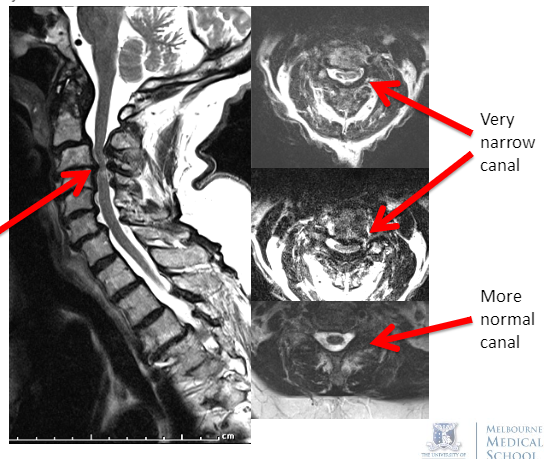

Hx and Ex suggest a slowly progressive compressive lesion of the cervical spinal cord (a classic “cervical myelopathy”)

In an older patient with neck pain, slow Sx onset, no fever and no Hx of cancer, this is most likely due to degenerative cervical canal stenosis

MRI: severe cervical canal stenosis with cord signal change due to disc prolapse, spondylosis and hypertrophy of the ligamentum flavum